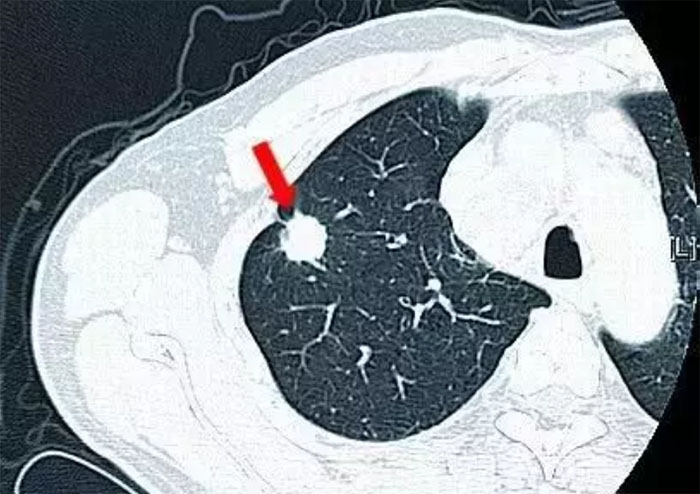

众所周知,肺癌的可怕之处就是出现临床症状时(如胸闷、刺激性干咳、咳血等),往往预示着肺癌已不是早期,这就需要“胸部CT”与“肺结节自身抗体检测”的结合,从影像学及分子生物学两方面,更加准确的对病灶进行综合评估与定性,从而达到“早发现、早诊断、早治疗”的目的。经各研究和随访的数据统计,肺结节自身抗体检测阳性率预测值可达88%。

① 结果为【CT(+),抗体(+)】,需临床干预。

②结果为【CT(-),抗体(+)】或【CT(+),抗体(-)】,需定期复查CT。

③ 结果为【CT(-),抗体(-)】,肺部健康。